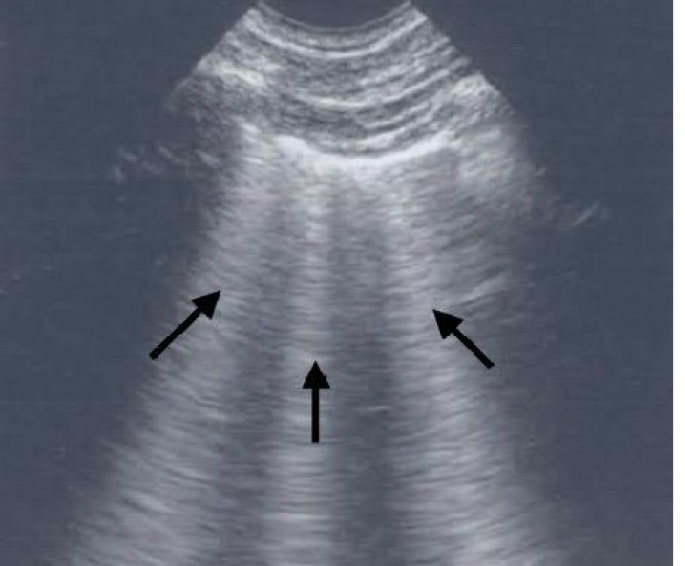

Detecting and monitoring EVLW in these patients is a challenging and difficult task. As mentioned earlier, clinical examinations are less sensitive and specific for early detection. Over the last few years, there has been growing interest in utilizing the LUS for detecting pulmonary congestion. The rationale behind its use is that water accumulation in the lung interstitium thickens the interlobular septa. This thickening produces a reverberation of the ultrasound beam and produces bundles that spread from the probe to the edge of the screen, often referred to as ring-down artifacts. (Fig. 3) These bundles are the true ultrasound equivalent of B-lines found in chest X-rays, and their simple count provides an estimate of pulmonary congestion. The number of B lines is strongly associated with various echocardiographic parameters, including left atrial volume, LV end diastolic volume, pulmonary artery pressure, E/E’ ratio, and ejection fraction. This association continues to be true pre- and post-hemodialysis. This implies that these associations are largely independent of excess fluid at single point in time. It is actually chronic volume excess which causes structural changes to myocardium over period of time. Moreover, increased B-lines are associated with increased mortality and cardiovascular complications, independent of other risk factors11.